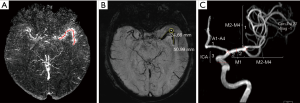

Primary SWI data with complete phase and magnitude images were processed using one button with SMARTv1.0 (susceptibility mapping and phase artifacts removal tool; Detroit, MI, USA) software within 30 s. The processing steps are detailed below. First, the unwanted low signal regions outside the brain were removed by a Brain Extraction Tool (BET) in FMRIB Software Library (FSL) (31). Second, the background phase was reduced by a 96×96 homo-dyne high-pass filter. Finally, SWIM data were generated by a truncated k-space division with a regularization threshold of 0.1 (32). The SWIM data were then observed and measured by signal processing in nuclear magnetic resonance (SPIN) (Detroit, MI, USA) software. The portions of M1 (initial and horizontal segment), M2 (Sylvian segment), and M3 (cortical segment) were marked, and susceptibility was manually measured. The detailed measurements are displayed in Figure 2A. The susceptibility of each segment was used to calculate the overall mean susceptibility of the multi-segmental thrombus. Thrombus length and CBS were measured on the SWI MinIP images along the segment of thrombus (5,33,34). The detailed measurements are shown in Figure 2B,C and Figure 3. DWI-ASPECTS was evaluated depending on the DWI and ADC images, according to the criteria of CT-ASPECTS (35,36). All of the measurements were repeated 3 times to calculate an average value by a neuroradiologist of 10-year experience and one of 5-year experience who both specialize in diseases of the central nervous system. The two readers were blinded to clinical data. The mean value of the two readers would be used if there were good consistency between them.